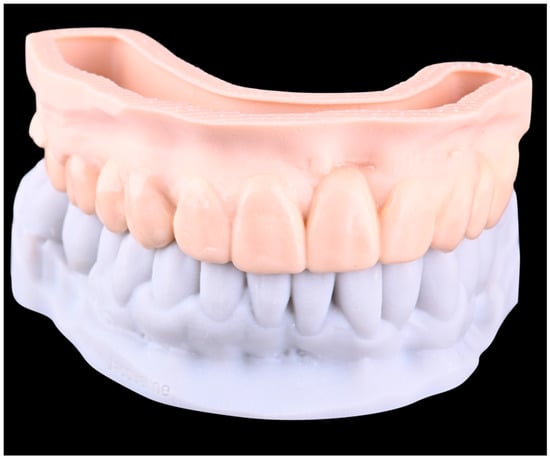

A digital diagnostic wax-up was created, and models were printed out (i.e., additively manufactured) of resin (Dental Model, ASIGA, Alexandria, Australia) with the proposed shape (Figure 4).

Figure 4. Printed diagnostic wax-up.